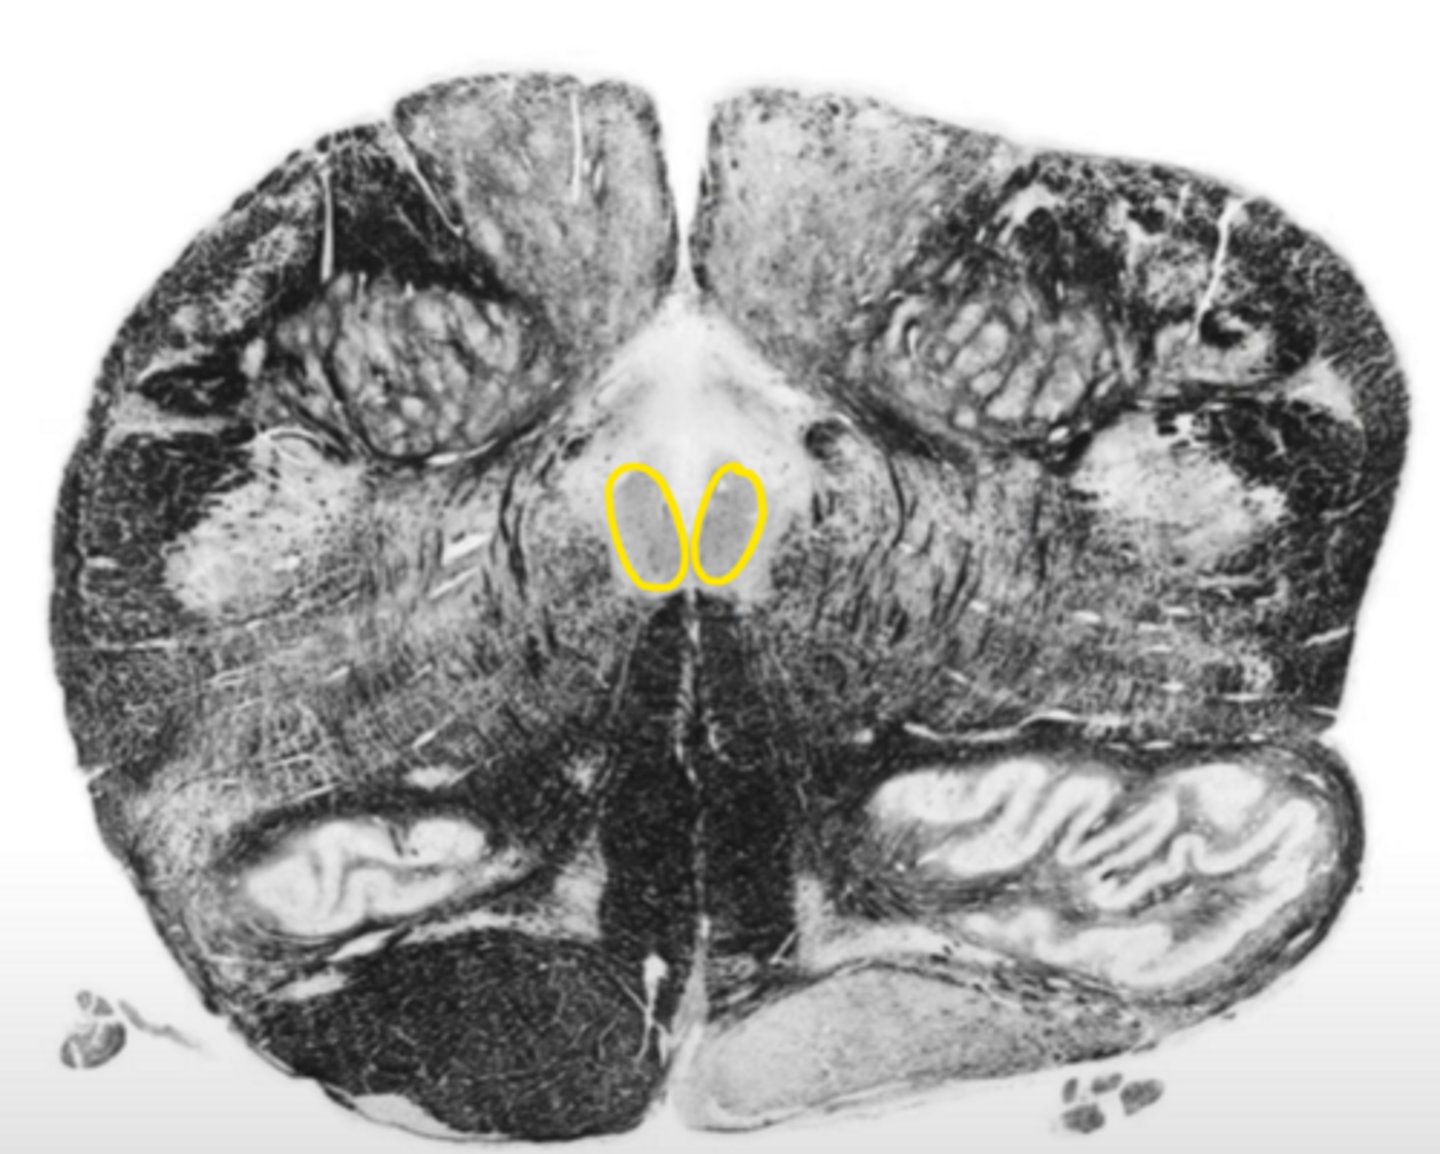

central canal

ID the space

central gray

ID the structure

hypoglossal nucleus

ID the nucleus

gracile nucleus

cuneate nucleus

inferior cerebellar peduncles

reticular formation

internal arcuate fibers

ID the fibers

principle olivary nucleus

medial lemniscus

corticospinal fibers

anterior median sulcus